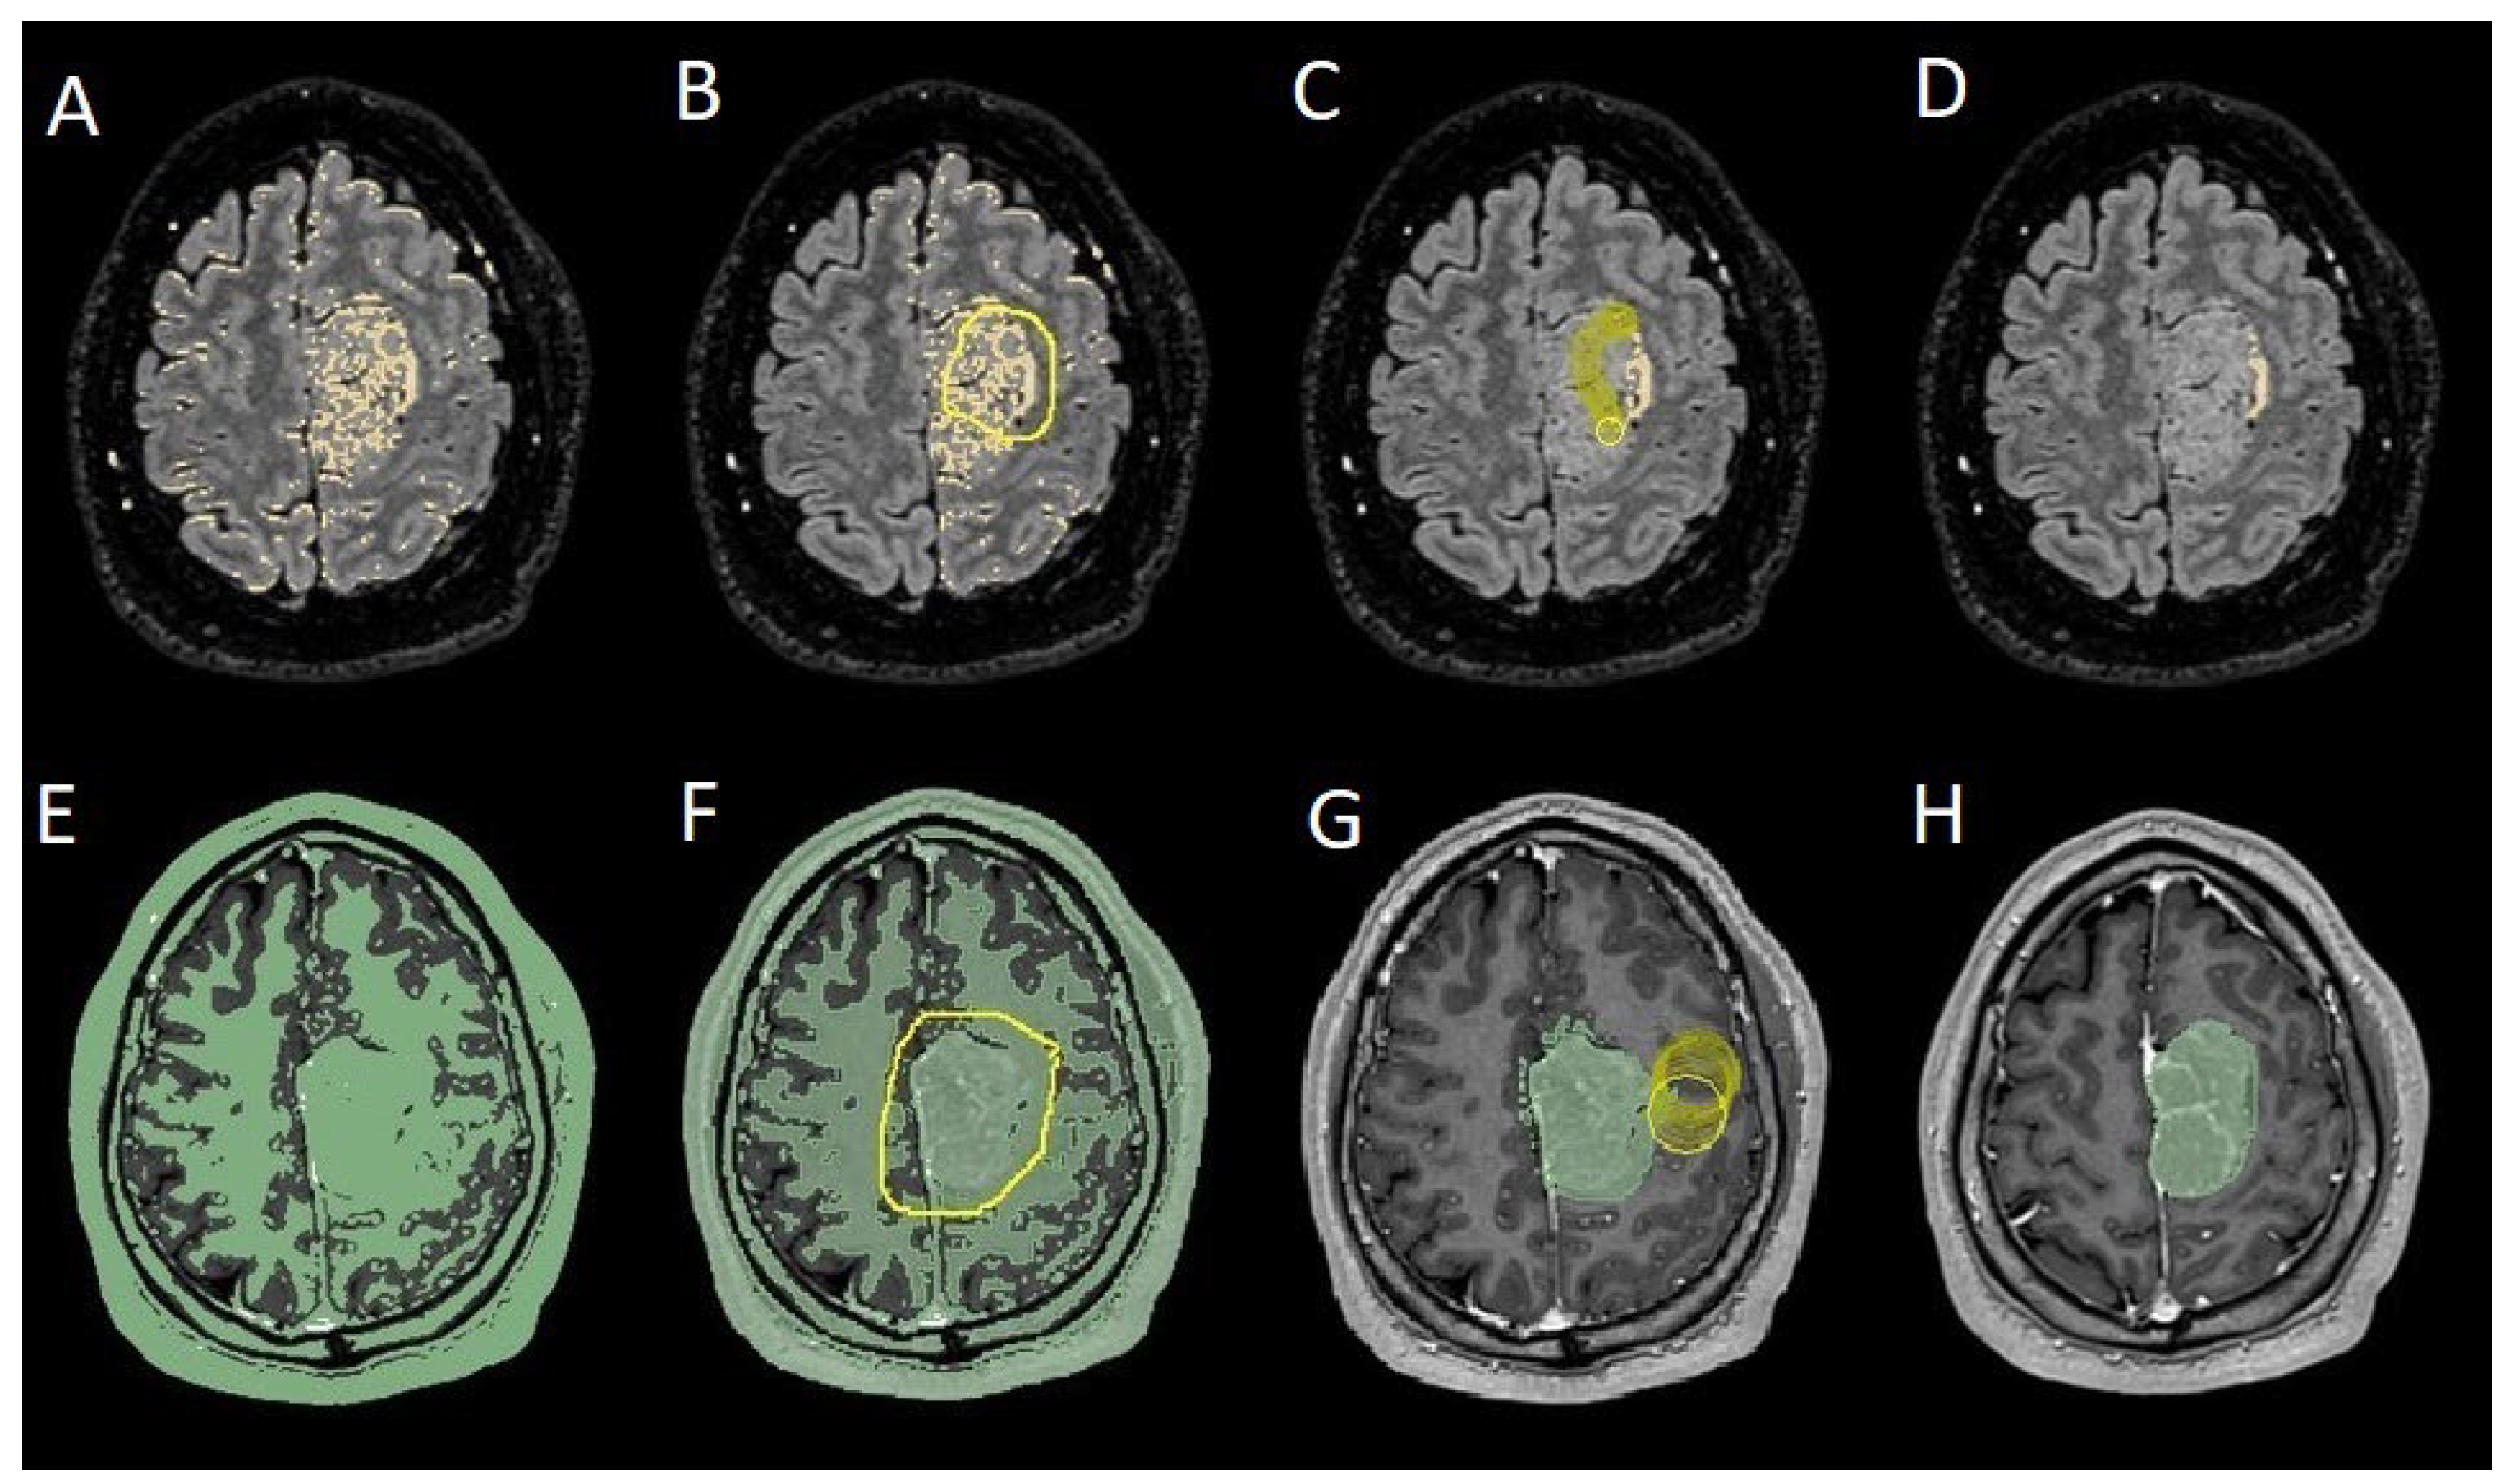

To evaluate which independent variables (meningioma volume, PE volume, the ratio between meningioma and PE volume, and the presence of preoperative epilepsy) influenced the dependent variable (seizure outcome), we performed a binomial logistic regression, which required converting continuous variables into binary values. For PE volume, values < 1 cm³ were coded as 0 (Figure 4), and values ≥ 1 cm³ as 1 (Figure 5). The cut-off was set at 3 cm³ for tumore volume, and for the volume ratio, the cut-off was 1. The absence of preoperative epilepsy was coded as 0, while its presence was coded as 1. Regarding seizure outcome, Engel IA cases were coded as 0, and cases classified as Engel >IA were coded as 1.

Figure 5. Segmentation process for PE > 1 cm3: A, E: automatic thresholding technique to identify initial regions of interest based on intensity values, respectively, for the PE and the meningioma; B, F: partially automatic erase of redundant signal with "erase outside" tool; C: precisely definition of boundaries of edema through manual erasement, cutting all around redundant signal inside the tumor; G: manual erasing boundaries for tumor volume; D, H: final segmented volumes. PE: peritumoral edema.